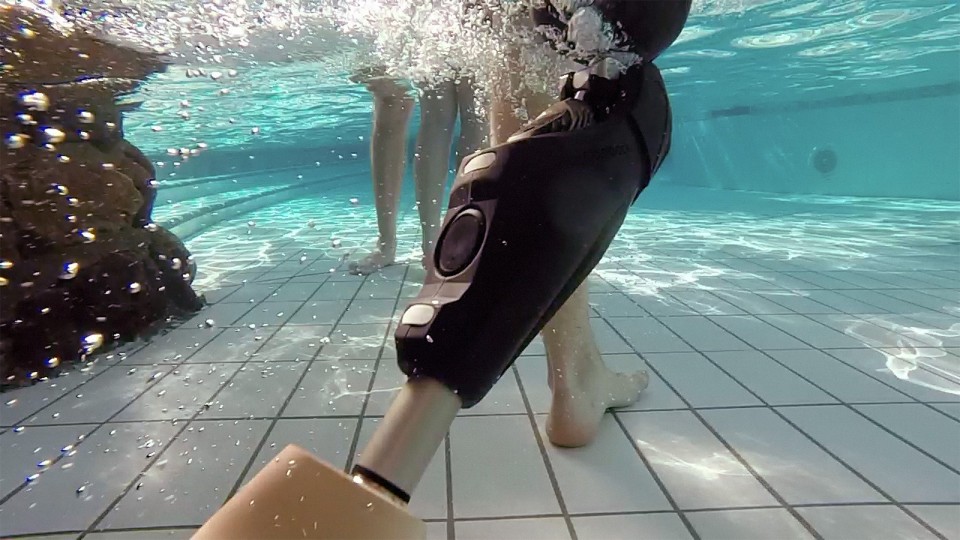

Eine Amputation ist die Entfernung eines Körperteils, meist von Armen oder Beinen, wenn eine so starke Schädigung vorliegt, dass eine Heilung nicht möglich ist und der Verbleib des Körperteils für den Betroffenen lebensbedrohlich wäre.

Ziel ist die optimale Prothesenversorgung zur Teilhabe an der selbstständigen Lebensführung

Unser Sanitätshaus geht einen eigenen Weg in der Prothesenversorgung. Dazu haben wir bestens ausgebildete Techniker und Physiotherapeuten im Team. Unser Anspruch ist es neueste Versorgungstechnik und perfektes Handwerk zu bieten. Die in allen modernen Prothesenanwendungen geschulten Physiotherapeuten stehen für eine nachhaltige Gebrauchsschulung.

Prothesen für den Vor und Rückfuß, Unterschenkel und Oberschenkel